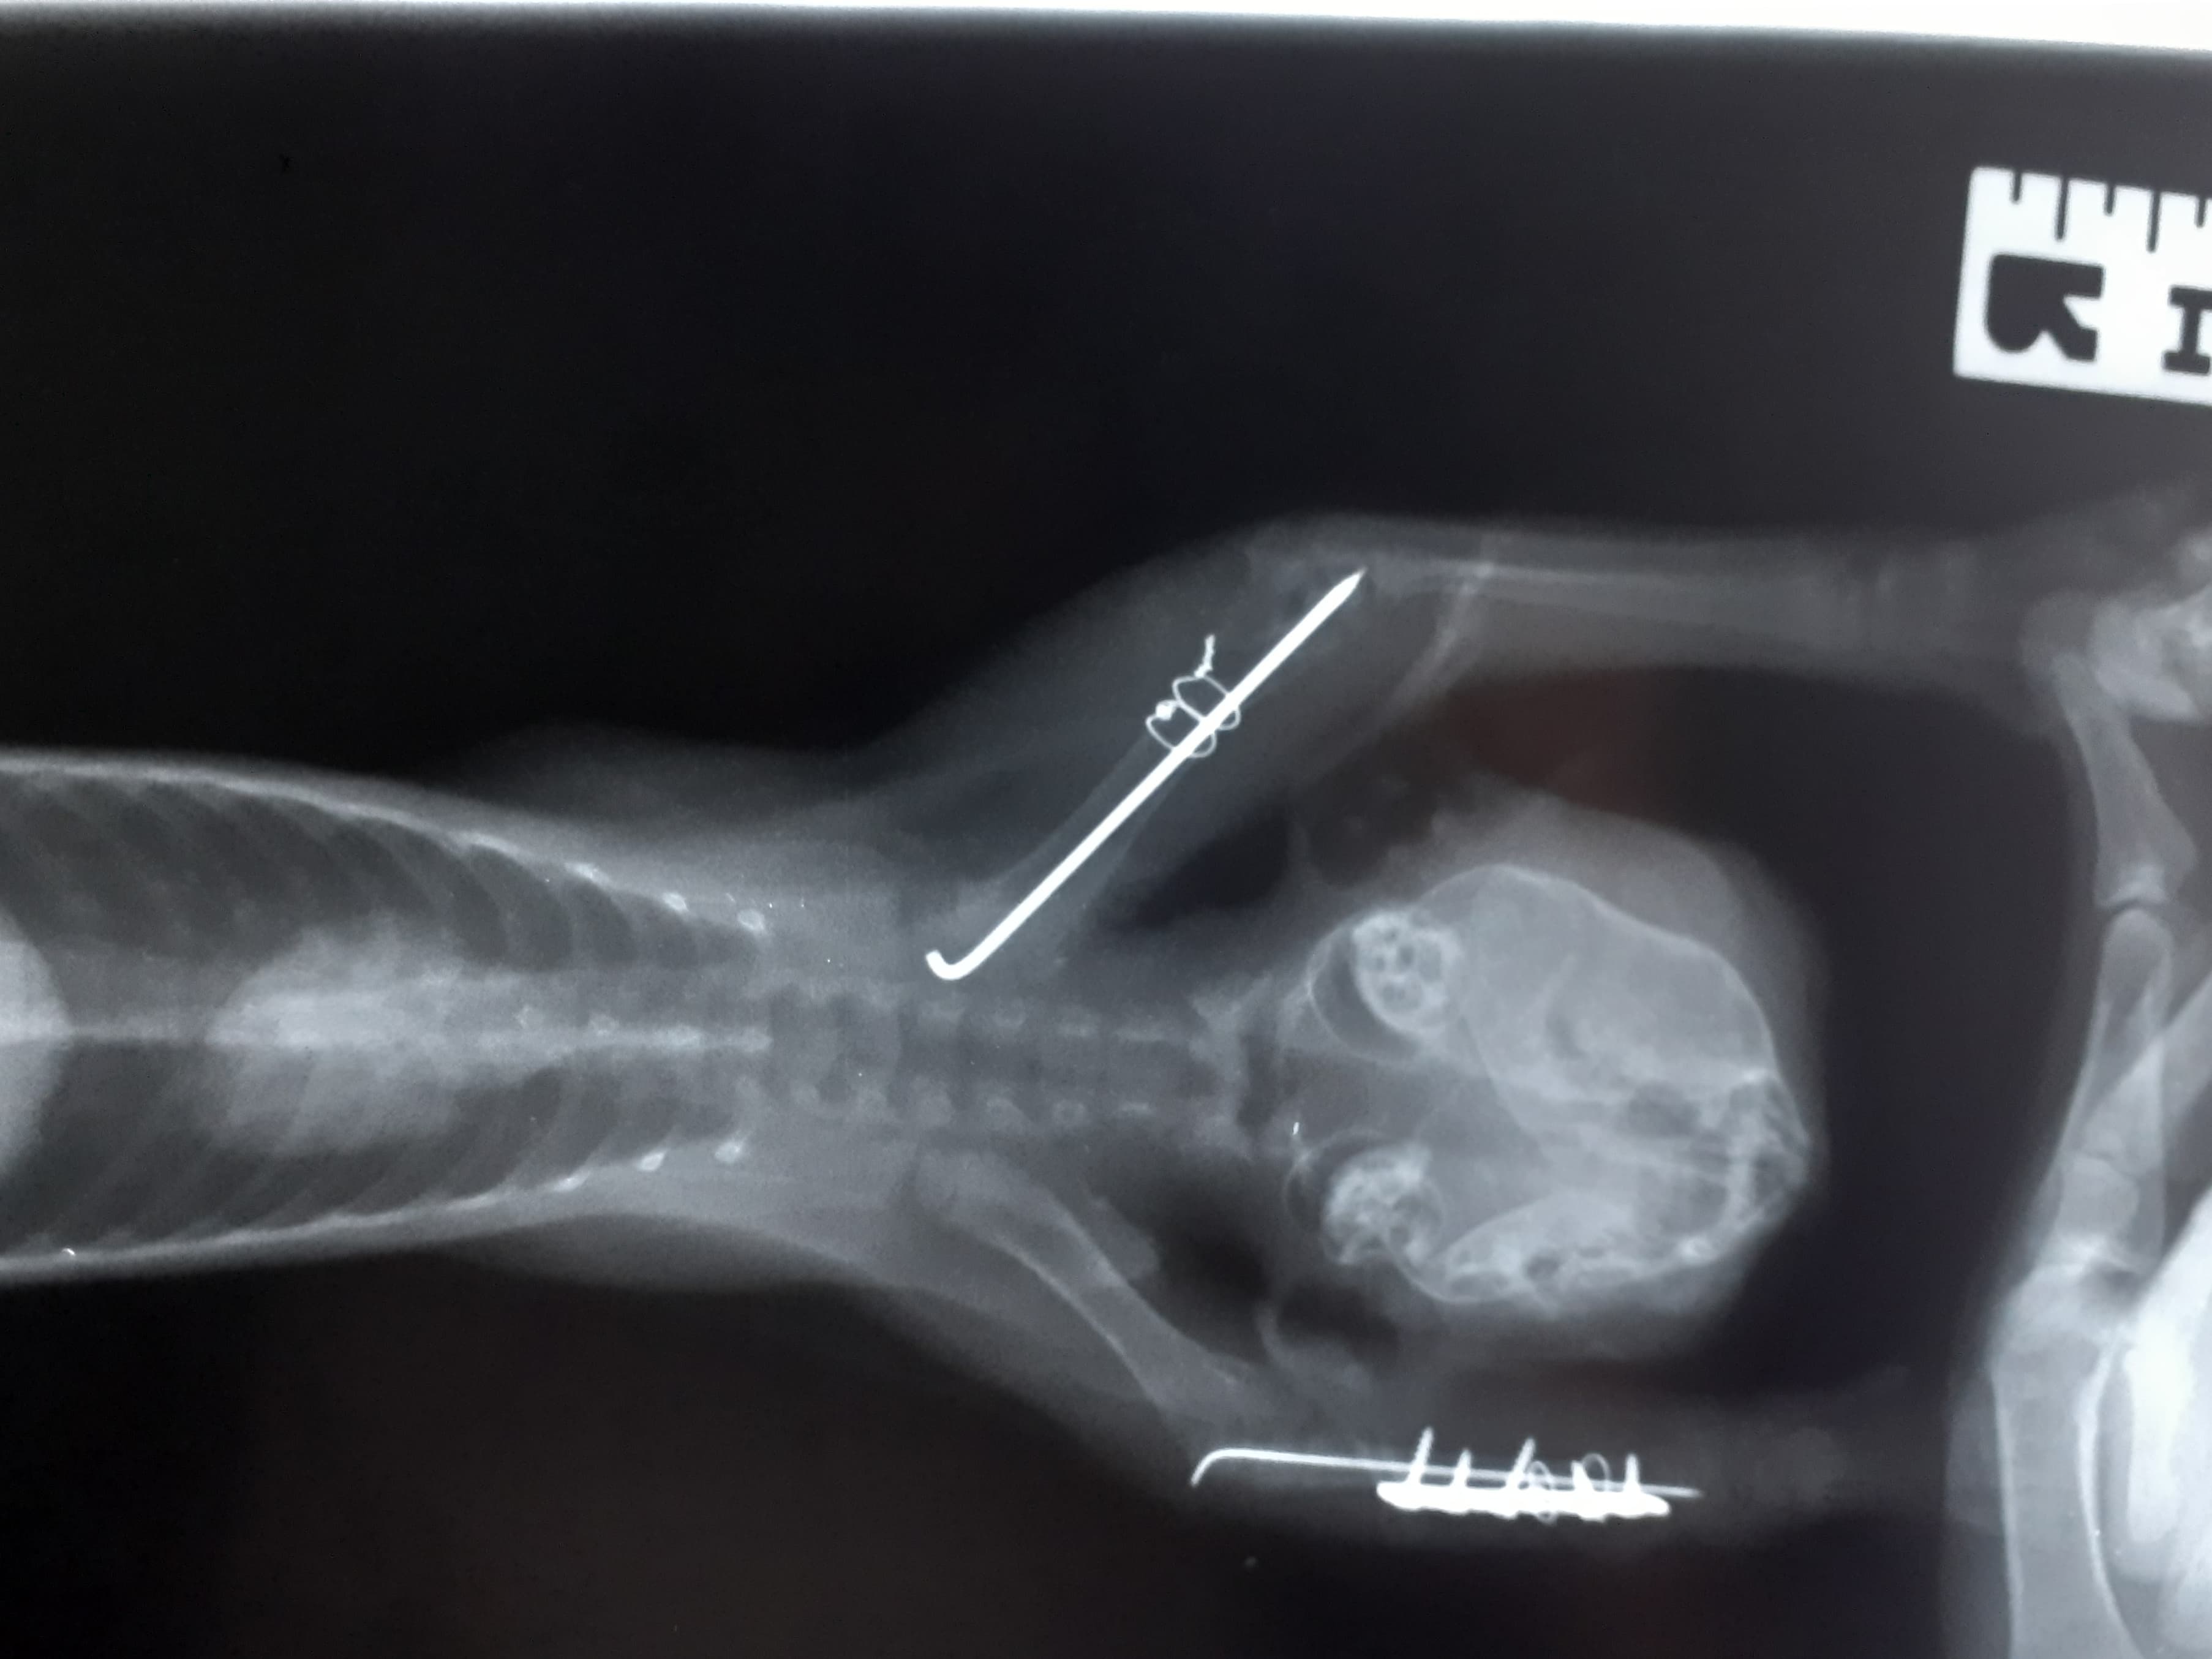

The poor little kitten we admitted to our care yesterday has a name! It's a girl and her name is Alex. 🐱 The kitten is hospitalised at the vet, she got infusion and already underwent broken legs surgery. Those were strenghtened by a wire and secured. Now it's time for Alex to lie calmly and heal, but she hasn't won her fight yet - there's still a risk of infection. 😔 We firmly hope nothing like that happens and everything will go smoothly from now on, but only time will tell. 🙏 As for the injured eye, the vet thinks it's glaucoma, but can't be sure yet. Despite the situation, the little one has a great zest for life - and even greater zest for food. ❤️ Even though she can't move too much, she manages to eat on her own. She's a great warrior. 💪 And she must feel so relieved right now. Yesterday morning, she wasn't sure what will happen with her and if she will even live another day. And now she's surrounded by people who are doing everything in their power to help her heal. ❤️ You are one of them and we want to thank you a lot for it and for all your support. 🙏

We picked up the kitten and took it to the local vet, where it got an injection for pain relief and the vet examined it and treated its eye. Then we took it to our vet who did a surgery on its legs. The vet also told us the kitten is a girl. We named her Alex.Please, help us save the kitten and send any amount to cover the veterinary costs. 🙏 We will do everything in our power to save it, but we can't do it alone. Please, join us. 🙏